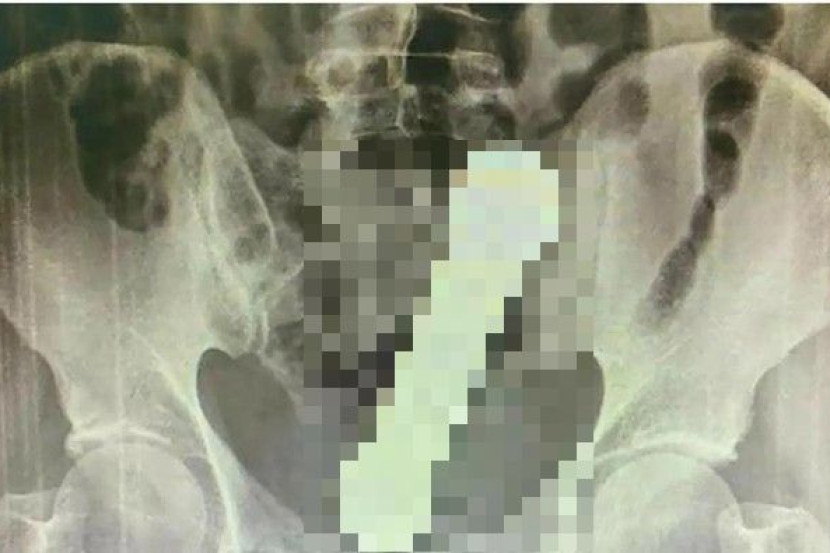

Selepas pemeriksaan awal gagal mendedahkan apa-apa, doktor memutuskan untuk membuat imbasan x-ray pada kawasan tersebut.

Mereka menjumpai dumbbell sepanjang 20 sentimeter (cm) terletak di persimpangan kolon dan rektum lelaki itu.